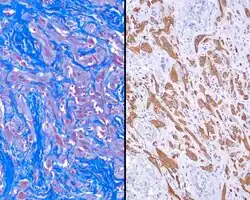

A trichrome stain will highlight the dual components well, with the glial tissue staining red, while the background fibrosis stains a bright blue.[2]

The glial tissue is highlighted with S100 protein and with glial fibrillary acidic protein, although the latter is much more sensitive for glial tissue.[2]